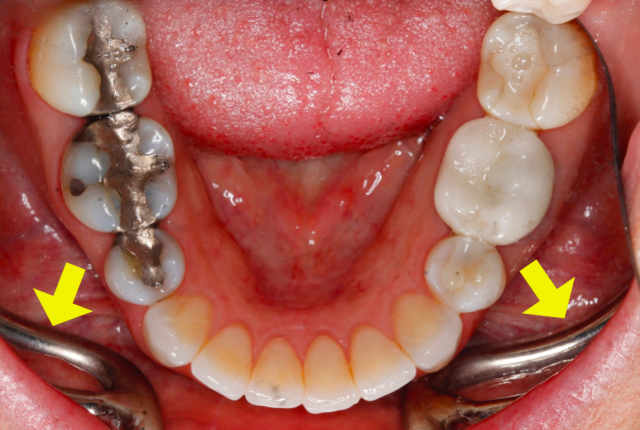

The best way to see everything, including the second molars, is to have the patient open really wide.

I work at getting my framing and focus right while asking the patient to simply “open.” Because it takes a few seconds to get this just right, I don’t have the patient open as big as I need them to until the very last second. Right before I take the shot, I hit the patient with this line: “Open your biggest big!” and I snap quickly. You’ll get a surprising amount of additional opening with this little gem.